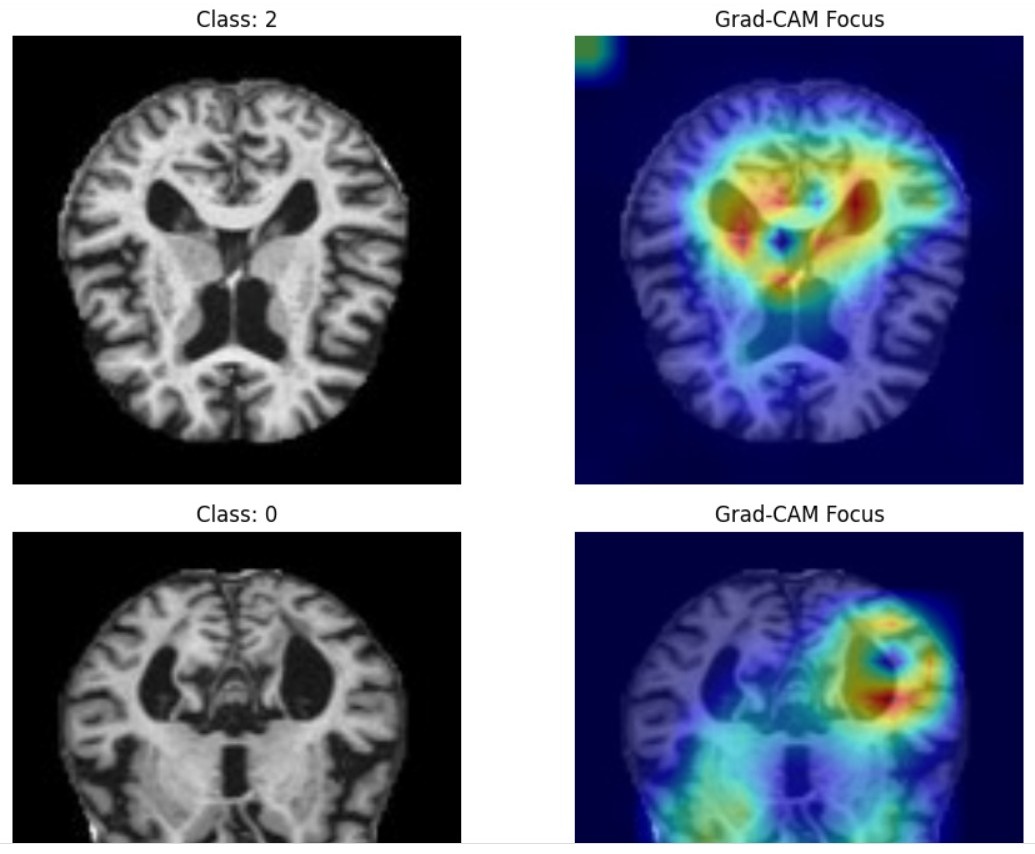

NeuroSense is an AI-powered system that classifies Alzheimer’s disease severity into four stages—Non-Demented, Very Mild, Mild, and Moderate—using structural MRI scans. The model aggregates multiple MRI slices per patient to generate a single, patient-level prediction and produces Grad-CAM heatmaps to explain which brain regions influenced each decision.

NeuroSense leverages an EfficientNetV2-based deep learning architecture for slice-level MRI feature extraction, followed by patient-level aggregation using mean pooling. This design enables robust severity prediction while preserving clinical context across slices. Integrated Grad-CAM explainability reveals model attention over key Alzheimer’s-related regions, including the hippocampus and temporal lobes, ensuring transparency and clinical relevance.

Key challenges included preventing data leakage across patients, handling class imbalance, and ensuring that high accuracy did not come at the cost of interpretability. Implementing patient-level aggregation and validating Grad-CAM outputs against known Alzheimer’s biomarkers were critical steps.